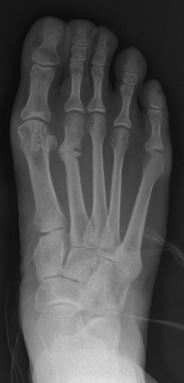

| Stress fracture of the second metatarsal bone (below the knuckles of the second toe) | |

Stress fractures can be described as small cracks in the bone, or hairline fractures. Stress fractures of the foot are sometimes called "march fractures" because of the injury's prevalence among heavily marching soldiers.[2] Stress fractures most frequently occur in weight-bearing bones of the lower extremities, such as the tibia and fibula (bones of the lower leg), metatarsal and navicular bones (bones of the foot). Less common are stress fractures to the femur, pelvis, and sacrum. Treatment usually consists of rest followed by a gradual return to exercise over a period of months.[1]